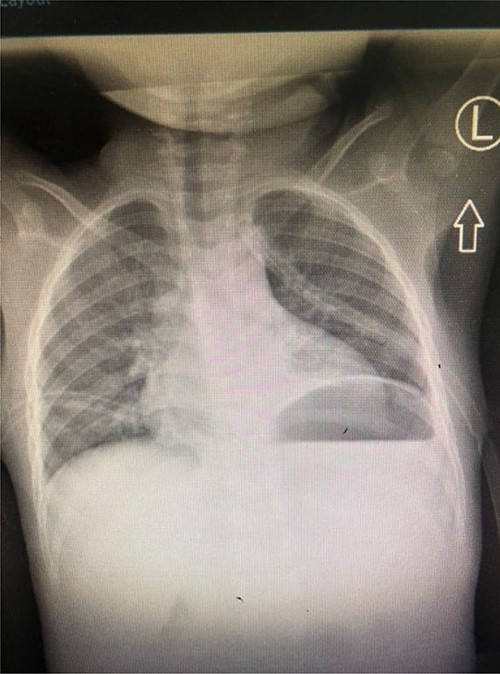

She was kept on conservative management with lipid restriction and octreotide. A day later, she had resolved respiratory signs and symptoms. Control computed tomography (CT) revealed significant improvements with minimal fluid on the left side (Fig. 3).

Axial Slice of the thorax showing bilateral thoracostomy tubes and minimal fluid on the left side (white arrow).

Diagnosis of chylothorax relies on clinical, radiological and biochemical confirmation of the chyle. Sudan III Stain has high fat globules affinity and may aid in establishing the diagnosis. Other methods include higher triglyceride’s measurement in chyle in comparison with plasma levels and lipoprotein electrophoresis [5]. Our patient had vivid milky fluid that had higher levels of triglycerides in comparison with plasma levels. Chest CT revealed minimal effusions following tube thoracostomies.